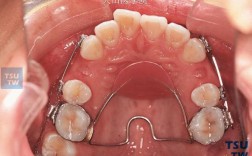

橡皮链的主要作用包括:关闭拔牙后的间隙、内收前牙、调整牙齿扭转、纠正中线偏移等,根据牙齿移动需求,医生可选择不同规格的橡皮链(如不同直径、弹性模量),通过连接托槽上的钩状结构或种植体附件,将力量作用于目标牙齿,其优势在于力量柔和且衰减缓慢(通常可维持1-2周有效力值),减少牙根吸收、疼痛等不良反应,同时操作简便,患者可部分自行更换(需医生指导)。

操作方法:在上下颌后牙区(如第二磨牙远中)植入微型种植体作为支抗,使用橡皮链一端连接种植体头部附件,另一端连接尖牙或前牙托槽的钩状结构,通过橡皮链的回缩力(约50-200g,根据牙齿移动需求调整)持续牵引前牙向远中移动,种植体支抗确保后牙几乎不前移,拔牙间隙被完全用于前牙内收,矫正效率显著提升(传统方法需6-12个月,结合种植体支抗可缩短至3-6个月)。